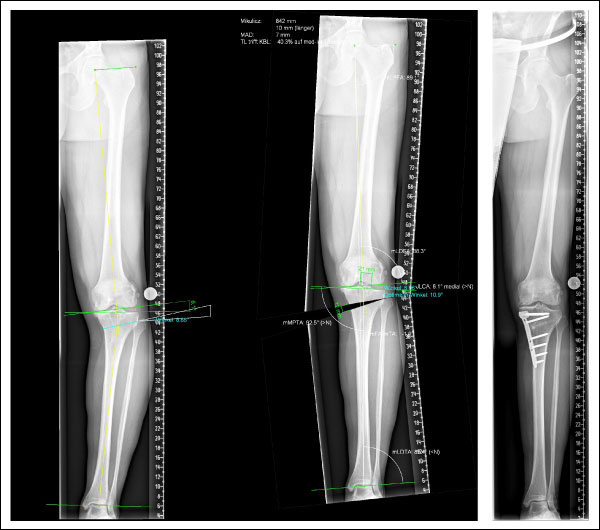

Bild 2: Hochgradige

O-Beinstellung

Bild 2 (anklicken zum Vergrößern): Hochgradige O-Beinstellung (Varus) des Beines (linkes Bild). Mitte: Planungszeichnung (Computersimulation) der Korrektur. Rechts: Durchgeführte Achskorrektur mit einer öffnenden Osteotomie und einer Platte am Tibiakopf.